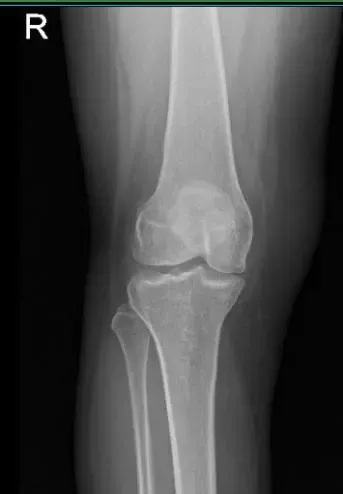

She presented her old X-ray done 8 months ago and suspected to have a medial meniscus tear of right knee. Suggested to take another X-ray/MRI to see the reason behind the pain. This time the patient agreed to take Cortisone injection to ease the pain somehow.

MRI of right knee

Patient returned and presented her MRI- found Tri compartment degenerative chest, with cartilage loss most pronounced in the patellofemoral compartment.

Complex tear involving the anterior horn lateral meniscus with a horizontal component extending into the body lateral meniscus with small joint effusion.